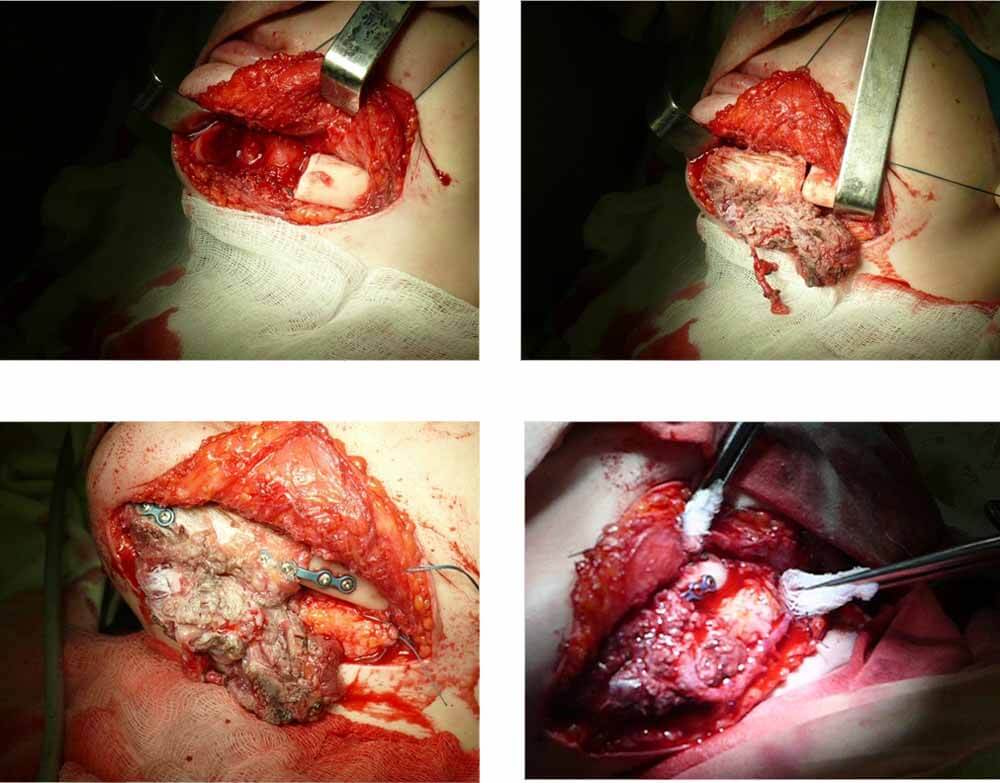

Пересадка тканевых комплексов самого пациента с возможностью замещения большого объёма отсутствующих тканей, как костных так и мягких.

лицевого скелета с трансплантацией мягких, костных и комбинированных тканей

Реабилитация пациента с Постонкологическим деффеком носа, с атрофией мягких тканей после лучевого лечения

На этапе лечения после реконструкции наружного отдела носа тканевым трансплантатом на сосудистой ножке

Постонкологический деффект носа, с атрофией мягких тканей после лучевого лечения